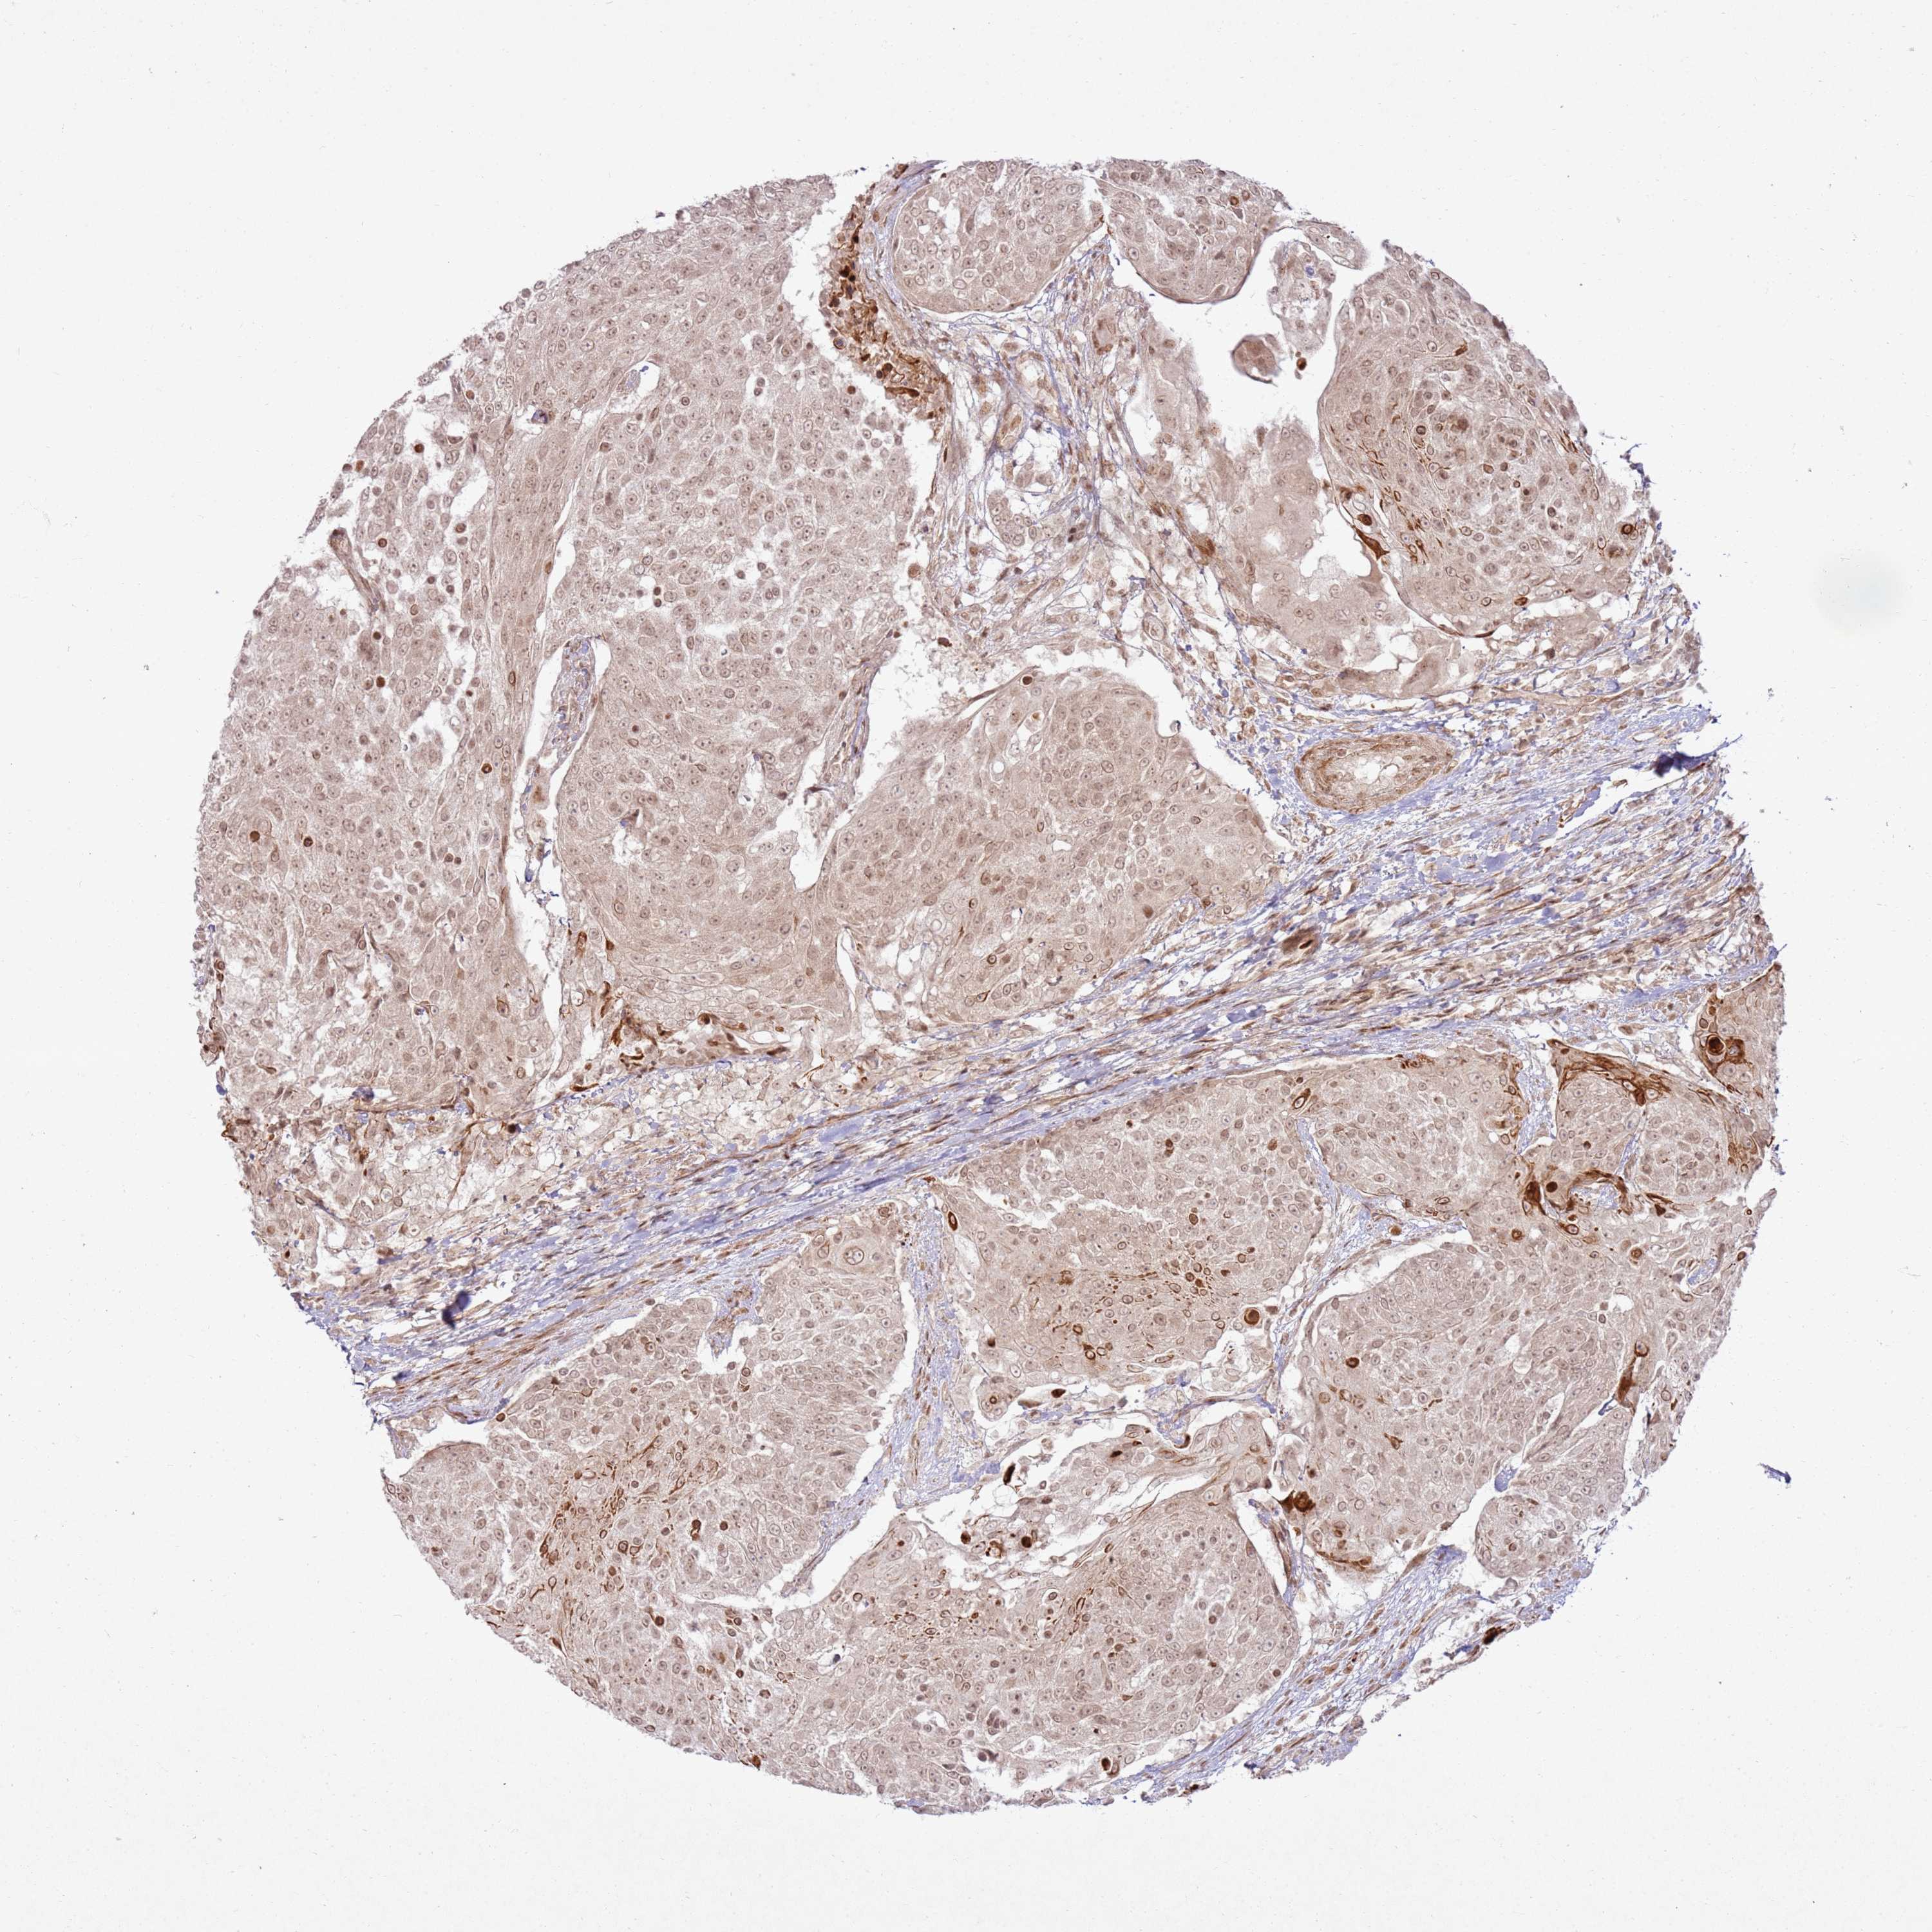

UROTHELIAL CANCER - Protein expressioni

A mouse-over function shows sample information and annotation data. Click on an image to view it in a full screen mode. Samples can be filtered based on level of antibody staining by selecting one or several of the following categories: high, medium, low and not detected. The assay and annotation is described here.

Note that samples used for immunohistochemistry by the Human Protein Atlas do not correspond to samples in the TCGA dataset.

Antibody stainingi

Antibody staining in the annotated cell types in the current human tissue is reported as not detected, low, medium, or high, based on conventional immunohistochemistry profiling in selected tissues. This score is based on the combination of the staining intensity and fraction of stained cells.

Each image is clickable and will lead to virtual microscopy that enables deeper exploration of all samples and also displays staining intensity scores, fraction scores and subcellular localization as well as patient and tissue information for each sample.

Antibody HPA023423

Staining

High

Medium

Low

Not detected

Intensity

Strong

Moderate

Weak

Negative

Quantity

>75%

75%-25%

<25%

None

Location

Nuclear

Cytoplasmic/membranous

Cytoplasmic/membranous,nuclear

Urothelial carcinoma, High grade

Urothelial carcinoma, Low grade